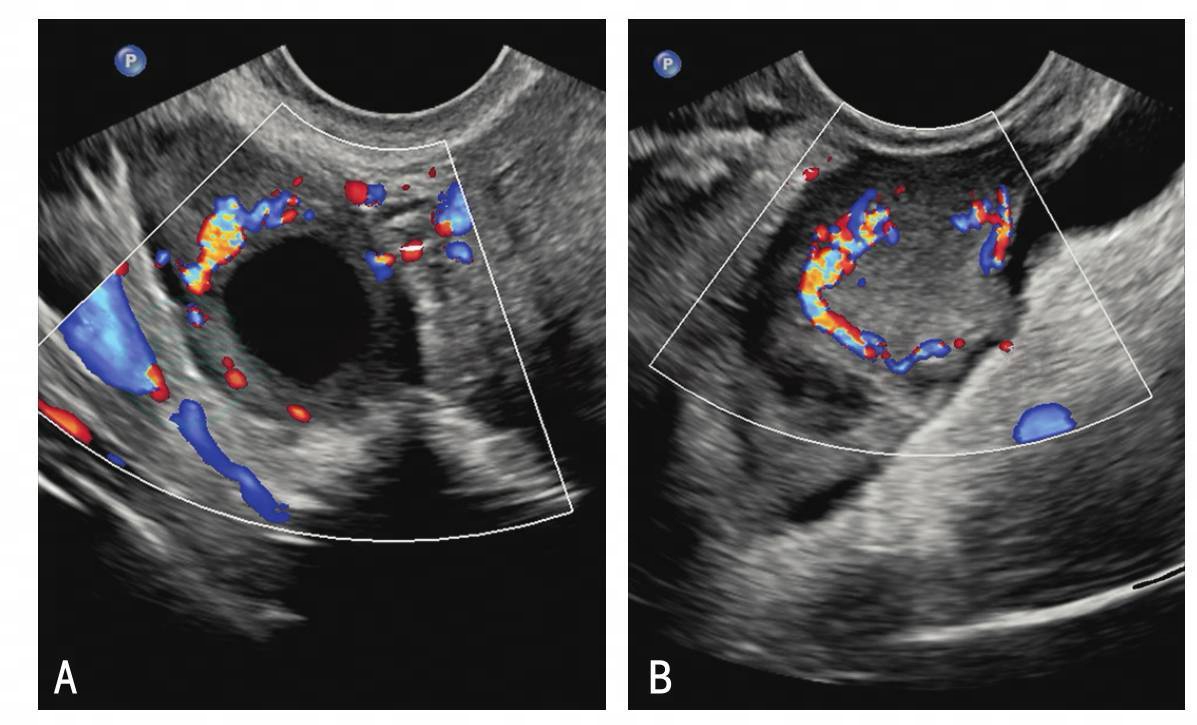

①月经期:双卵巢内可见数个窦卵泡(图2-3),卵泡直径在3~7mm;②增生期:一侧卵巢内可见优势卵泡发育,直径可达18~24mm,另一侧卵巢可无明显改变;③排卵期:一侧卵巢内优势卵泡因排卵转变为黄体,形成不规则环状低回声,其内透声差,壁厚。排卵前在优势卵泡壁上可见彩色血流信号,频谱多普勒可测到低阻血流。排卵后优势卵泡塌陷,转变为黄体,其周围可见环状血流信号,频谱多普勒为低阻血流频谱。根据黄体囊内出血量的不同和检查时间不同,黄体内回声可为无回声、网状低回声或云雾状不均回声等(图2-4)。

图2-4 卵巢内黄体声像

A.卵巢内黄体呈液性无回声,周围环状血流信号;B.卵巢内黄体呈实性稍高回声,周围环状血流信号